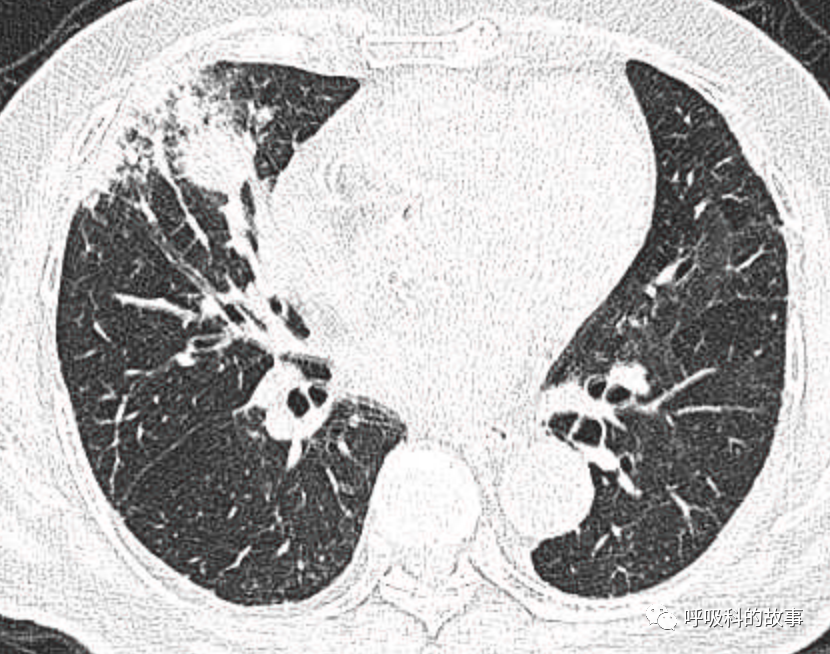

1个月前,我们收治了一个80多岁的男性患者,两肺多发结节和肿块,锁骨上淋巴结也触及肿大,在接诊时我们就预感不妙,患者很可能是患上了肺癌。后来经过穿刺后明确为大细胞神经内分泌癌,CT如下。

图1-11:该患者各个角度的影像图像

(上下滑动查看全部图片)